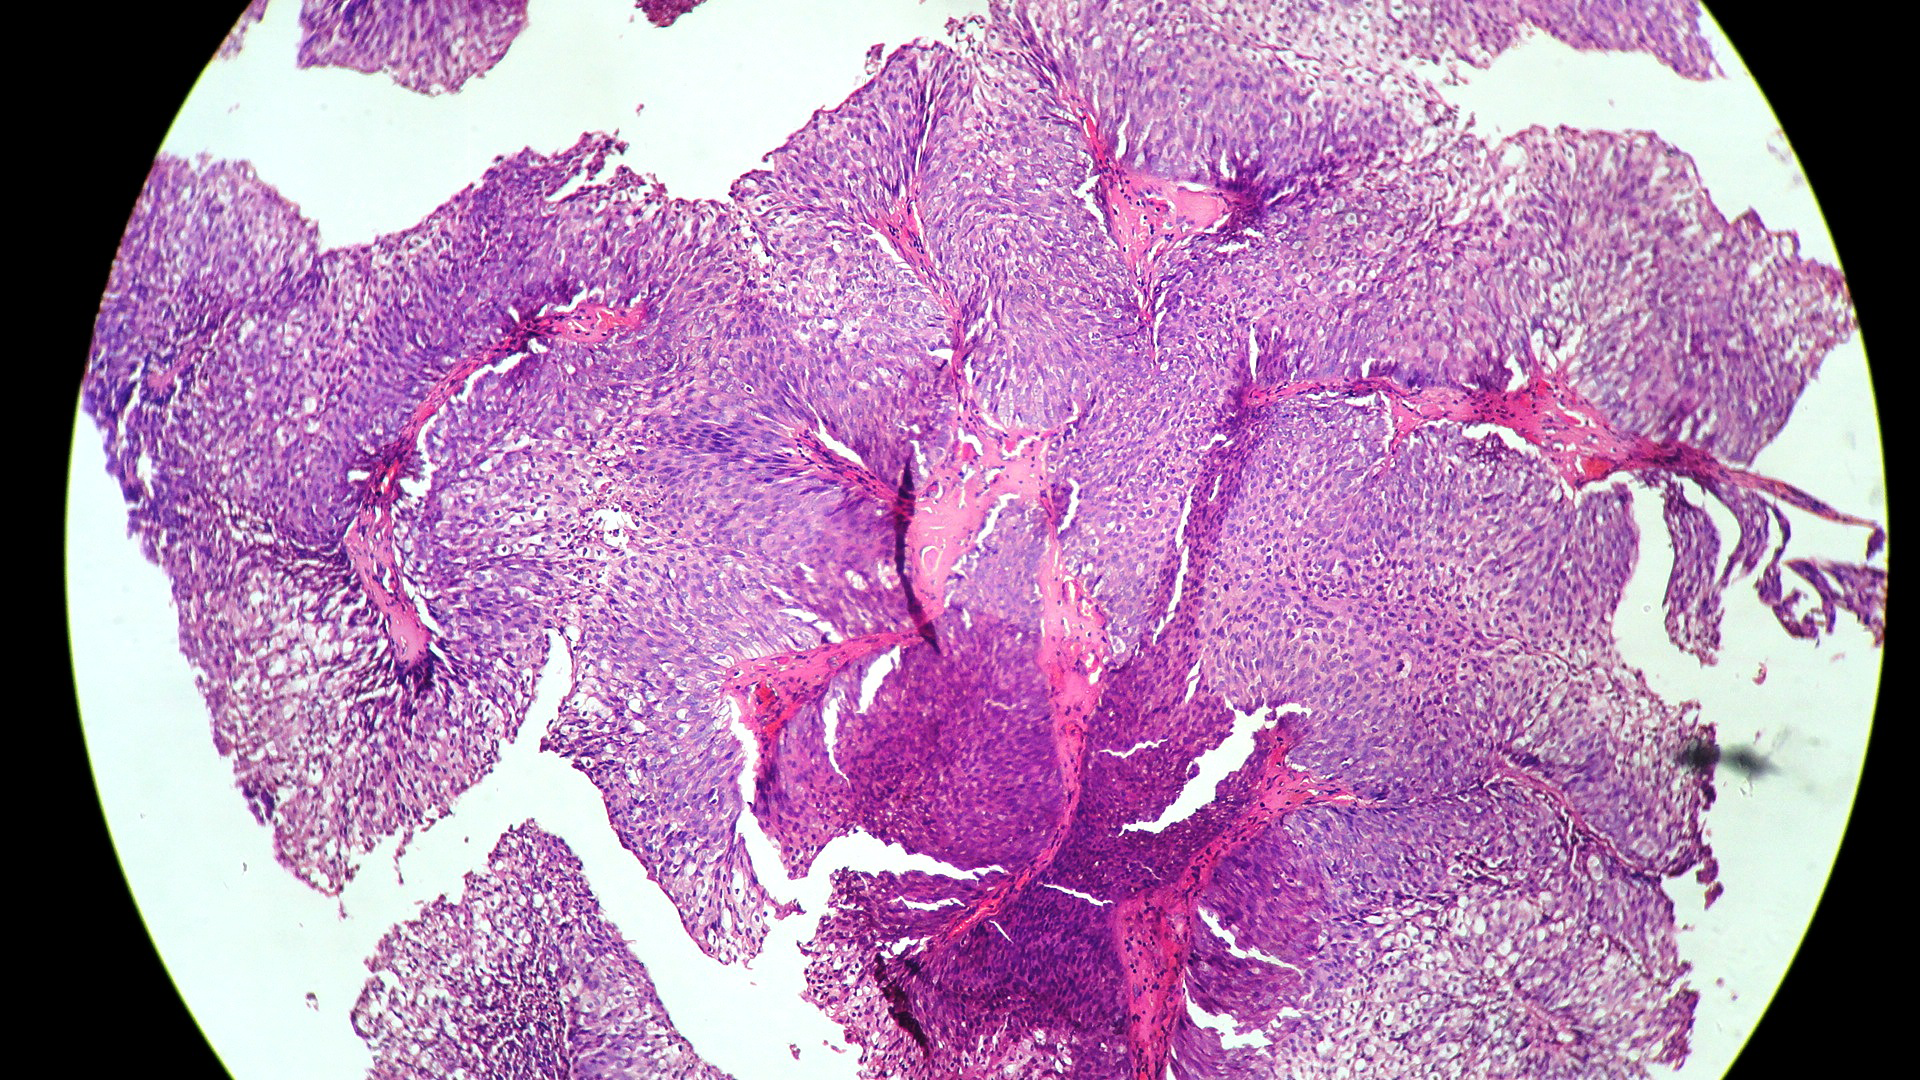

In our study, we made an attempt to evaluate the pattern of tumor growth, its degree of differentiation, progression and associated mucosal changes. In 15 cases of urothelial papilloma, it is characterized by discrete papillary growth with a central fibrovasular core lined by urothelium of normal thickness and cytology (Figure 1). In five cases of Papillary urothelial neoplasm of low grade malignant potential (PUNLMP), histopathologically the tumor is characterized by delicate, orderly, tenuous papillary structures with orderly arrangement of cells within the papillae with minimal architectural abnormalities and nuclear atypia usually limited to basal layer irrespective of cell thickness (Figure 2). The major distinction from papilloma is that in PUNLMP the urothelium is much thicker and nuclei are significantly enlarged. In 21 cases of low grade urothelial carcinoma, histologically it is characterized with papillary axes which are more compact, crowded, fused at the base and lined by unordered cells showing both architectural and cytological abnormalities with frequent mitosis (Figure 3). In 51 cases of high grade urothelial carcinoma showed fused papillary axes over the large areas resulting in sheets and solid areas. The cells have enlarged, hyperchromatic, pleomorphic nucleus in full thickness of the epithelium with increased atypical mitosis (Figure 4). As per TNM staging used in our study we observed majority of the bladder tumours were invasive accounting for 78.25% (Figure 5 & 6) as compared to non-invasive bladder tumours constituting 21.73% of the cases as shown in table 3.

Figure 1 Urothelial papilloma showing discrete papillae lined by normal thickened urothelium with normal cytology (H and E stain, 100X).